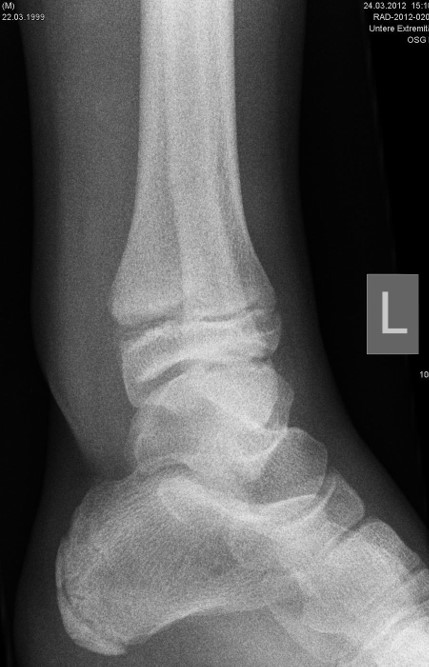

Übergangsfrakturen

Übergangsfrakturen sind spezielle Verletzungen, die ausschließlich in der Lebensphase beobachtet werden, in welcher die Wachstumsfugen teilweise geschlossen sind. Die Wachstumsfuge an der distalen Tibia schließt sich von ventromedial beginnend nach dorsal und lateral. Während die bereits geschlossene Wachstumsfuge eine hohe Stabilität aufweist, ist der knorpelige Anteil der noch offenen Fuge wesentlich weniger widerstandsfähig. Die mechanisch schwächste Schicht der Wachstumsfuge ist der Blasenknorpel. Durch Biege- und Scherkräfte kommt es zu einer Verletzung der Wachstumsfuge mit Aussprengung eines metaphysären Keils. Übergangsfrakturen sind „unvollendete“ Fugenschaftfrakturen bei welchen die bereits geschlossene Fuge ein Auslaufen der Frakturlinie durch die Fuge verhindert und daher die Bruchlinie ins Gelenk ausläuft (v. Laer 2013).

Rein epiphysäre Frakturen werden als Twoplane-Frakturen bezeichnet. Der Frakturverlauf liegt in der Epiphyse und dem noch nicht verknöcherten Anteil der Wachstumsfuge. Gibt es noch einen zusätzlichen metaphysären Keil handelt es sich um eine Triplane-Fraktur. Bei einer Triplane-Fraktur kann sich in Einzelfällen die metaphysäre Fraktur bis in die Epiphyse fortsetzen, sodass eine zusätzliche Querfraktur resultiert. Es entsteht der Eindruck eines zusätzlichen hinteren Volkmann Fragments.

In Abhängigkeit vom Reifezustand der Wachstumsfuge kann der epiphysäre Frakturspalt sehr weit medial bis ganz lateral zu liegen kommen. Ein sehr weit lateral liegender Frakturspalt entspricht funktionell nahezu einem knöchernen Ausriss der vorderen Syndesmose, was sich im Röntgenbild an einer erweiterten Malleolengabel erkennen lässt 9